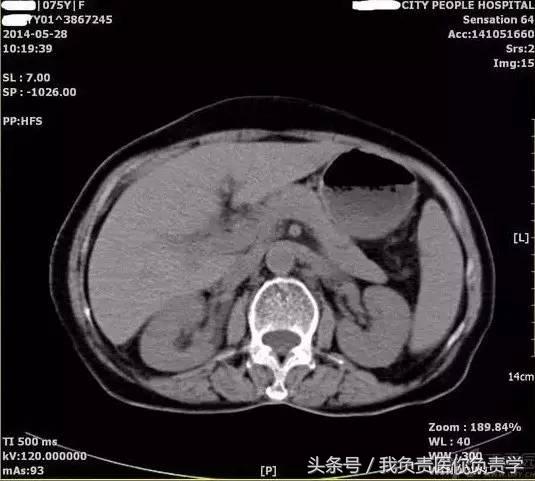

图6和7为相应CT表现